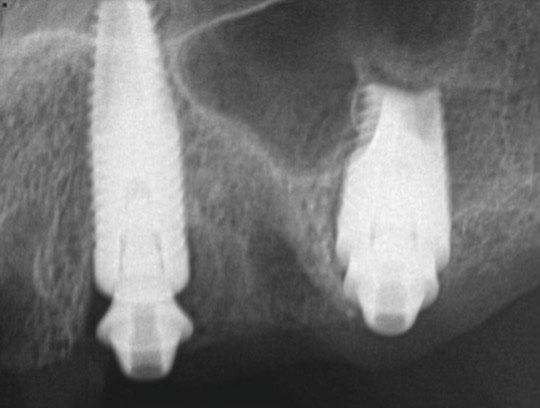

Fig 21. Postoperative panoramic radiograph on the day of surgery.

Figure 21

Fig 22. Postoperative periapical x-rays on the day of surgery demonstrating the provisional restoration with ti-bases fully seated to multi-unit abutments and ideal immediate implant placement.

Figure 22